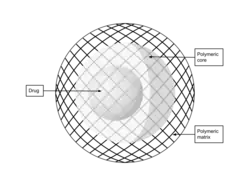

Polymer-based nanoparticles

Polymer-based nanoparticles can be made from either natural or synthetic sources. Nanospheres and nanocapsules are polymeric nanoparticle systems. Natural polymers can be found in the environment or human body. On the other hand, synthetic polymers do not occur naturally and are artificially developed polymers with chemical modifications. Natural polymer-based nanoparticles can be made up of chitosan, hyaluronic acid, alginate, and gelatin. Natural polymers exhibit excellent biocompatibility and biodegradability, and low toxicity. Synthetic polymer-based nanoparticles can consist of polyglycolic acid (PGA), poly (lactic acid) (PLA), and poly(lactide-co-glycolide) (PLGA).

A study evaluated chitosan nanoparticles loaded with an anti-epileptic drug, phenytoin (PHT), to treat epilepsy. Observations suggested high stability, sustained release, and bioavailability when these particles where administered via the intranasal route.[41] Similarly, administering PLGA nanoparticles loaded lamotrigine (LTG), polymer-based nanoparticle, showed better permeation through BBB and higher bioavailability.[42]